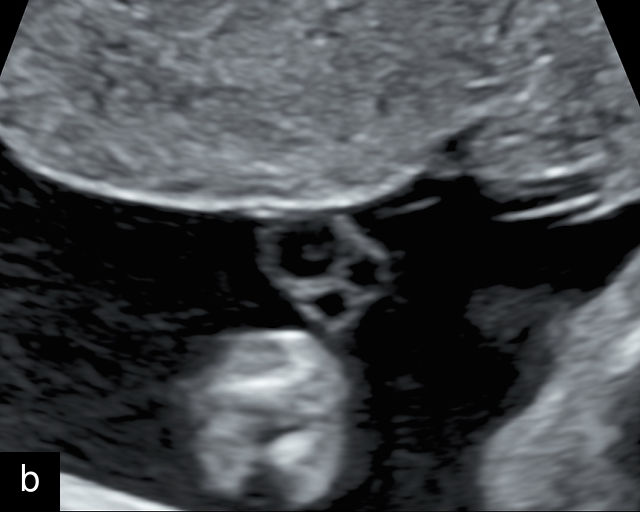

The umbilical cord serves as the lifeline connecting the fetus to the placenta. It arises from the midportion of the fetal abdomen and typically inserts into the center of the placenta (Figure 16). The average length of the umbilical cord is approximately 55 cm (22 inches).185 It contains three vessels: two arteries, which originate from the fetal left and right internal iliac arteries, and one vein, collectively referred to as a three-vessel cord.

16

Normal appearance of the umbilical cord with two umbilical arteries and a single vein. (a–c) Cross-section of the umbilical cord on grayscale (a,b) and power Doppler (c) ultrasound. In the normal cord, three vessels are visible: a larger umbilical vein and two smaller umbilical arteries. This characteristic appearance is often referred to as the 'Mickey Mouse' sign, the larger circle (umbilical vein) representing Mickey’s face while the smaller circles (arteries) form his ears. (d–g) Grayscale (d) and color Doppler (e–g) images of transverse section of the lower fetal abdomen showing the two umbilical arteries diverging around the fetal bladder. (h) Longitudinal ultrasound view with color Doppler of a normal umbilical cord showing three vessels present in each coil: two arteries with flow in one direction and a single vein with flow in the opposite direction.

At a minimum, the mid-trimester ultrasound should include identification and documentation of the umbilical cord's fetal and placental insertions, as well as the number of cord vessels.66,186,187 In a transverse grayscale section of the cord, the two umbilical arteries can be visualized alongside the larger, thinner-walled umbilical vein, creating a characteristic ‘Mickey Mouse’ appearance (Figure 16a–c). Additionally, in a transverse section of the lower fetal abdomen, the umbilical arteries are seen encircling the fetal bladder. This can be seen on grayscale ultrasound and confirmed with color flow Doppler (Figure 16d–g).